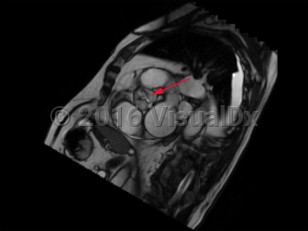

Aortic stenosis (AS) is the narrowing of left ventricular outflow through the aortic valve. It is the most prevalent cause of ventricular outflow obstruction, and it is increasing in prevalence as the population ages and life expectancy increases. While patients are generally asymptomatic in the presence of mild outflow obstruction, exertional dyspnea, chest discomfort, fatigue, dizziness, and syncope develop as the degree of obstruction progresses.

Contributing etiologies include calcification of the aortic valve cusps (most common in the elderly population), congenital abnormalities (ie, bicuspid aortic valve), rheumatic fever, chest radiotherapy, endocarditis, and alkaptonuria. Potential complications include heart failure, cardiac arrhythmias, infectious endocarditis, pulmonary hypertension, excessive bleeding, stroke, and other embolic events.